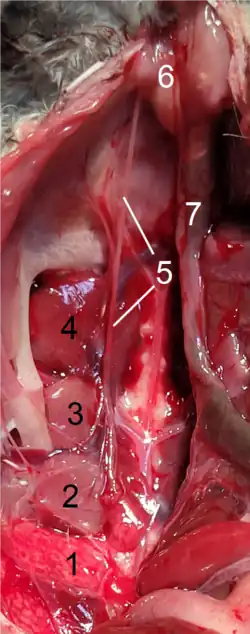

Der Harnleiter beginnt am Nierenbecken, in dem der von der Niere zuerst abfiltrierte und anschließend aufkonzentrierte Urin gesammelt wird. Am Ursprung knickt der Harnleiter um etwa 90° ab. Er läuft dann als Bauchteil (Pars abdominalis) im Retroperitonealraum auf dem gleichseitigen Musculus psoas major.[2][3] Er überquert den gleichseitigen Nervus genitofemoralis und unterquert dann bei der Frau die Eierstockarterie (Arteria ovarica), beim Mann die Hodenarterie (Arteria testicularis).[3] Etwa ab Höhe des fünften Lendenwirbels zieht der Harnleiter leicht zur Mitte hin.[4] Am Beckeneingang biegt er bauchwärts um und verläuft als Beckenteil (Pars pelvica, Synonym: Pars pelvina) in der Wand des „kleinen Beckens“ bis zur Harnblase. Er überkreuzt dabei zunächst die Aufzweigung der Arteria iliaca communis und unterkreuzt dann beim Mann den gleichseitigen Samenleiter, bei der Frau die gleichseitige Gebärmutterarterie (Arteria uterina).[3] Der Harnleiter hat bei Erwachsenen eine Länge von 25 bis 30 Zentimetern, Bauch- und Beckenteil sind etwa gleich lang.[5] Der Durchmesser beträgt 2 bis 7 Millimeter,[6] im Regelfall 3 bis 4 mm. Bei Neugeborenen ist der Harnleiter 6,5 bis 7 cm lang.[5]

Der rechte Harnleiter liegt in räumlicher Nähe zu Zwölffingerdarm, Ileum, Colon ascendens, Blinddarm und Wurmfortsatz, der linke zu Bauchspeicheldrüse, Jejunum, Colon descendens und Colon sigmoideum. Da genaue anatomische Landmarken zur Ortung des Organs fehlen, kann er bei Operationen am Colon und Mastdarm und insbesondere bei der laparaskopischen Entfernung der Gebärmutter versehentlich verletzt werden.[7][8] Die Harnleiter liegen beidseits bauchseitig des Nervus genitofemoralis, der rechte liegt seitlich der unteren Hohlvene (Vena cava inferior), der linke seitlich der unteren Mesenterialvene (Vena mesenterica inferior).[9]

Nach seinem Eintritt in die Harnblasenwand verläuft der Harnleiter zunächst eine kurze Strecke innerhalb dieser Wand (intramural). Dieser intramurale Abschnitt ist 0,5 bis 1 cm lang,[10] nach anderen Angaben 1,5 bis 2 cm.[3] Dann durchbohrt er die Blasenschleimhaut und mündet mit der Harnleitermündung (Ostium ureteris) in das Innere der Harnblase. Die schlitzförmigen Harnleitermündungen sind klappenartig geschlossen, wenn durch sie kein Urin tritt.[3] Der Verlauf in der Blasenwand verhindert bei stärkerer Füllung der Harnblase einen Rückfluss des Urins zur Niere (vesikorenaler Reflux).[11] Die beiden Harnleitermündungen begrenzen mit der unpaaren Harnröhrenöffnung im Inneren der Blase das Harnblasendreieck (Trigonum vesicae).[12]